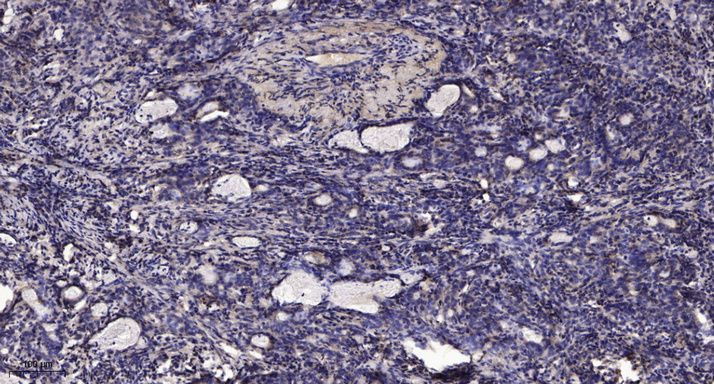

WB, IHC, IF, IP

Optimal working dilutions should be determined experimentally by the investigator; Suggested starting dilutions are as follows:IHC 1:50-300; IF 1:200.